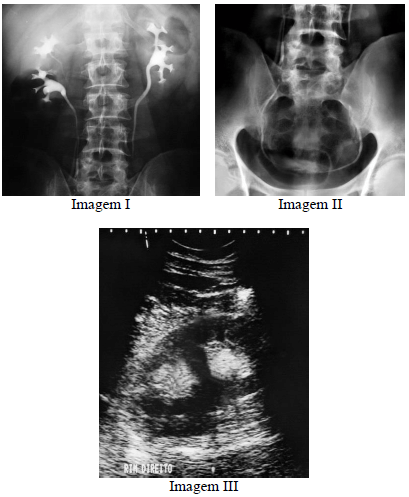

Considerando o diagnóstico evidenciado nas imagens precedentes, julgue o item a seguir.

A imagem III demonstra sinais típicos de duplicação pielocalicinal, sendo a ultrassonografia um método com alta sensibilidade, estimado em cerca de 90% para detecção dessa entidade.

Enunciado 3064456-1

A entidade demonstrada nas imagens está associada a aumento de incidência de estenose da junção ureteropélvica e de outras malformações geniturinárias.